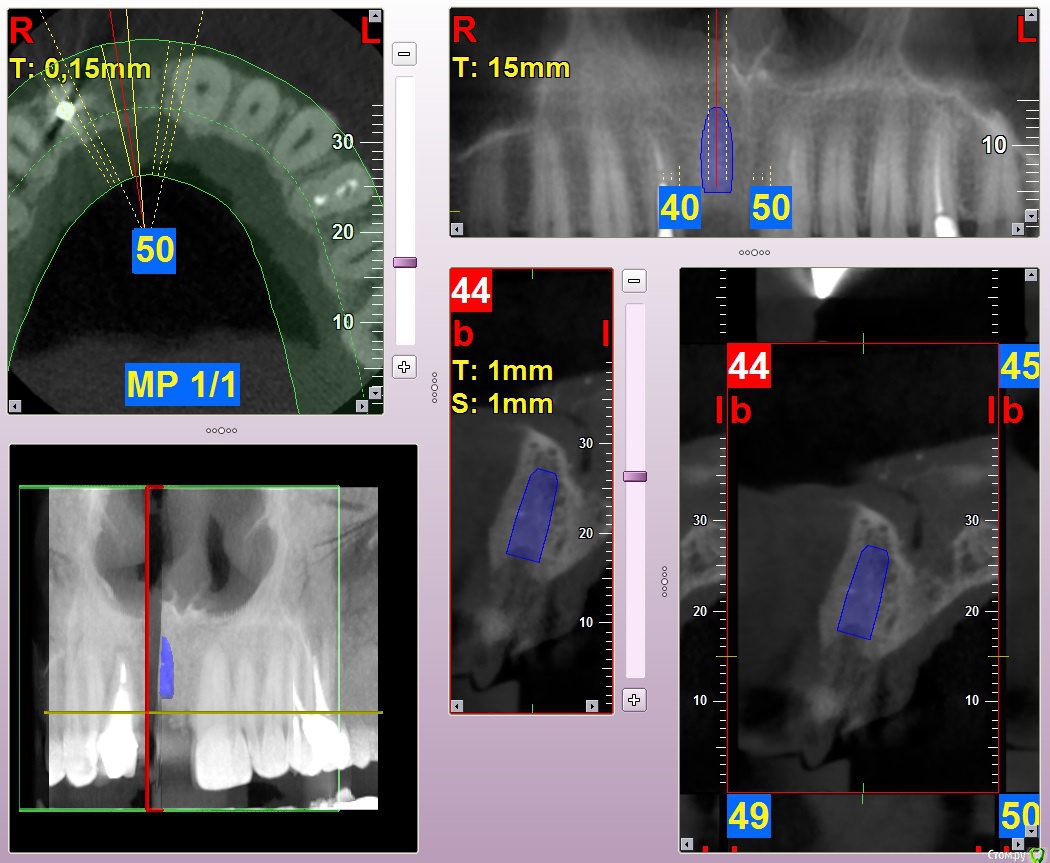

Kostoprav Опубликовано 8 июля, 2015 Автор Поделиться Опубликовано 8 июля, 2015 (изменено) продолжение истории) вот что было изначально а вот что получилось) временная реставрация она с ней до имплантации ходила, коронка на 12 тоже временная Изменено 8 июля, 2015 пользователем Kostoprav 3 Ссылка на комментарий

Kostoprav Опубликовано 8 июля, 2015 Автор Поделиться Опубликовано 8 июля, 2015 графт повторно после кюретажа засыпал) Ссылка на комментарий